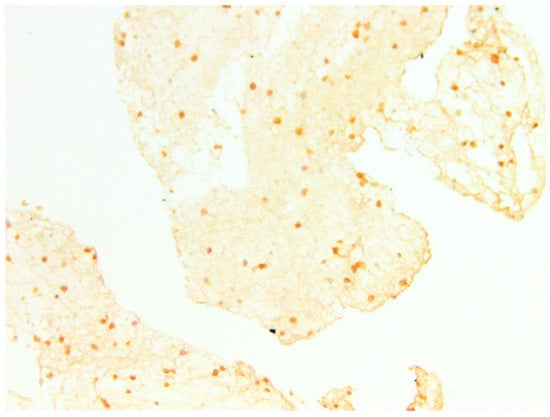

3.3. IHC Study

3.3.2. CD133

3.3.3. CD10

| % of Expression | CD133, Amount of Samples | Min Age | Max Age | Mean Age |

|---|---|---|---|---|

| 10 | 2 | 19 | 19 | 19.0 |

| 5 | 8 | 25 | 38 | 29.5 |

| 1 | 9 | 21 | 34 | 26.6 |

| 0 | 11 | 21 | 42 | 30.7 |

| % of Expression | CD10, Amount of Samples | Min Age | Max Age | Mean Age |

| 10 | 8 | 19 | 38 | 26.5 |

| 5 | 3 | 29 | 33 | 30.3 |

| 1 | 8 | 21 | 34 | 26.2 |